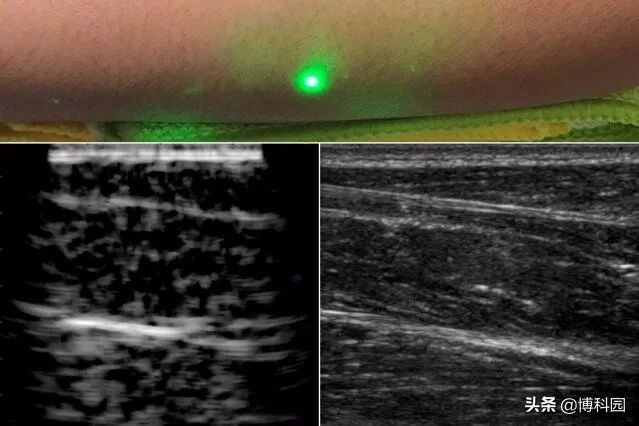

第二个激光器远程探测反射波,然后研究人员将其转换成类似于传统超声波的图像。在发表在《自然》和《光:科学与应用》期刊上的新研究中,研究小组报告了在人类身上首次产生激光超声波图像(图2)。研究人员扫描了几名志愿者的前臂,观察了常见的组织特征,如肌肉、脂肪和骨骼,低至皮肤下约6厘米。这些图像可以与传统超声波相媲美,是使用远程激光在半米外聚焦于一名志愿者而产生的。

最后,研究小组使用麻省理工学院人体实验委员会批准的方案,在人体上进行了第一次激光超声实验。在扫描了几名健康志愿者的前臂后,研究人员产生了第一个完全非接触式的人体激光超声图像。脂肪、肌肉和组织边界清晰可见,可与商用接触式超声探头生成的图像相媲美。研究人员计划改进技术,目前正在寻找方法来提高系统的性能,以解决组织中的精细特征,同时还在寻求磨练探测激光器的能力。研究人员希望将激光装置小型化,这样有朝一日激光超声波可能会被部署为便携式设备。